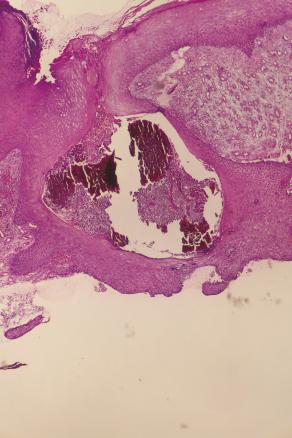

Cette femme de 65 ans, d’origine rurale, avait une tuméfaction du pied droit évoluant depuis 10 ans. L’examen notait une pseudotumeur, multinodulaire, polyfistulisée, de l’avant-pied (fig. 1 ) parsemée de grains noirs. L’examen mycologique des grains montrait des filaments. À l’histologie, on notait une hyperplasie épidermique pseudo-épithéliomateuse avec des structures brunâtres en grains entourées de polynucléaires neutrophiles au niveau du derme (fig. 2 ), permettant le diagnostic de mycétome fongique. Le bilan d’extension ne montrait pas d’atteinte osseuse. Un débridement chirurgical des tissus atteints (fig. 3 ) avec traitement systémique par itraconazole était réalisé. Une récidive était notée 1 an plus tard.